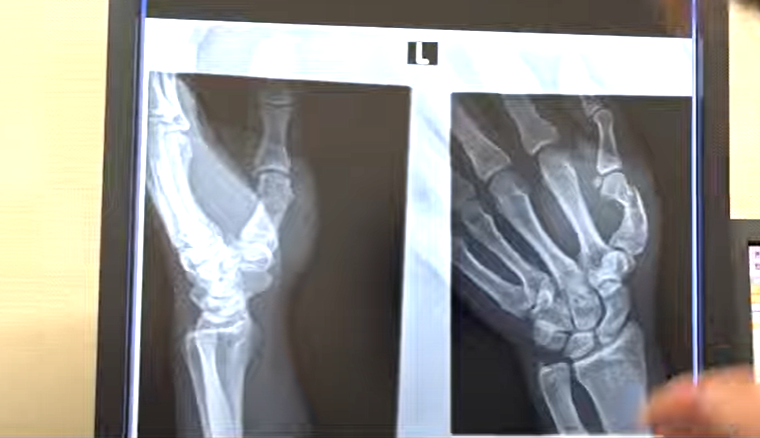

加藤の左手親指の骨折レントゲン写真(『エンセン井上Channel』)